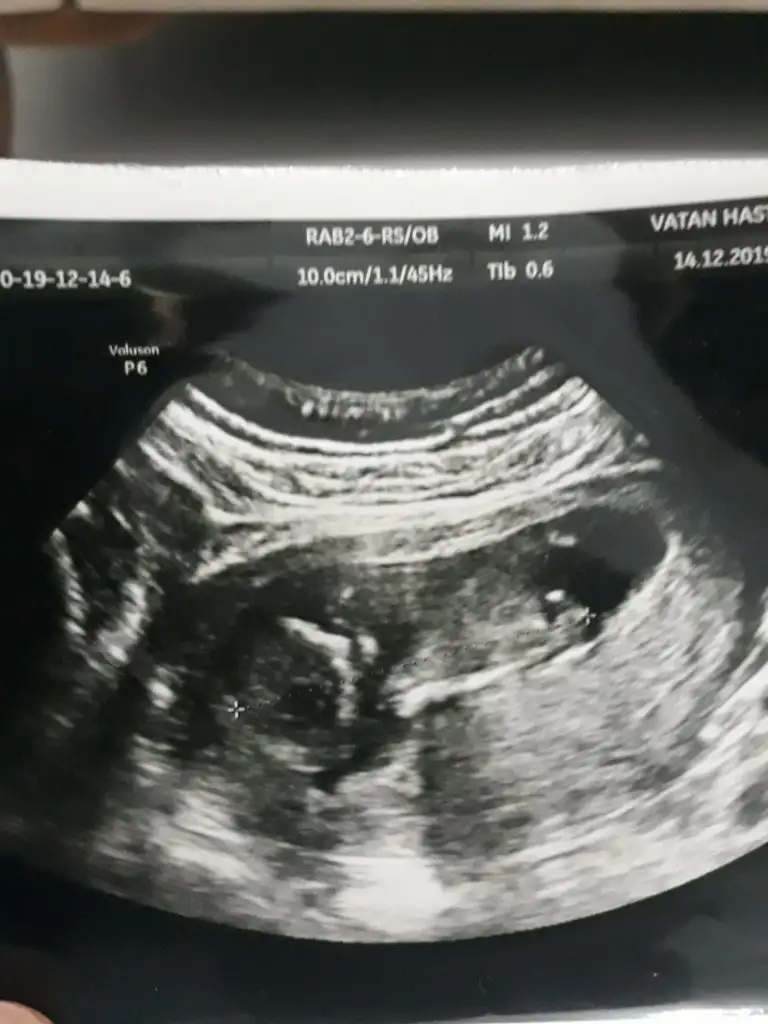

Buda bizim Nub umuz bı tahminde bulunur musunuz ☺️ bıraz karanlık cıktık ama olabıldiği kadar. Dr erkek dedı ilerleyen zamanda netlestırrız dedı. Sızcede oylemı tesekkürler .

Biri 9+5 digeri 11+5 doktor bacaklati kapali dedi resimde de sirti donuk sanki yanlis miyim☺